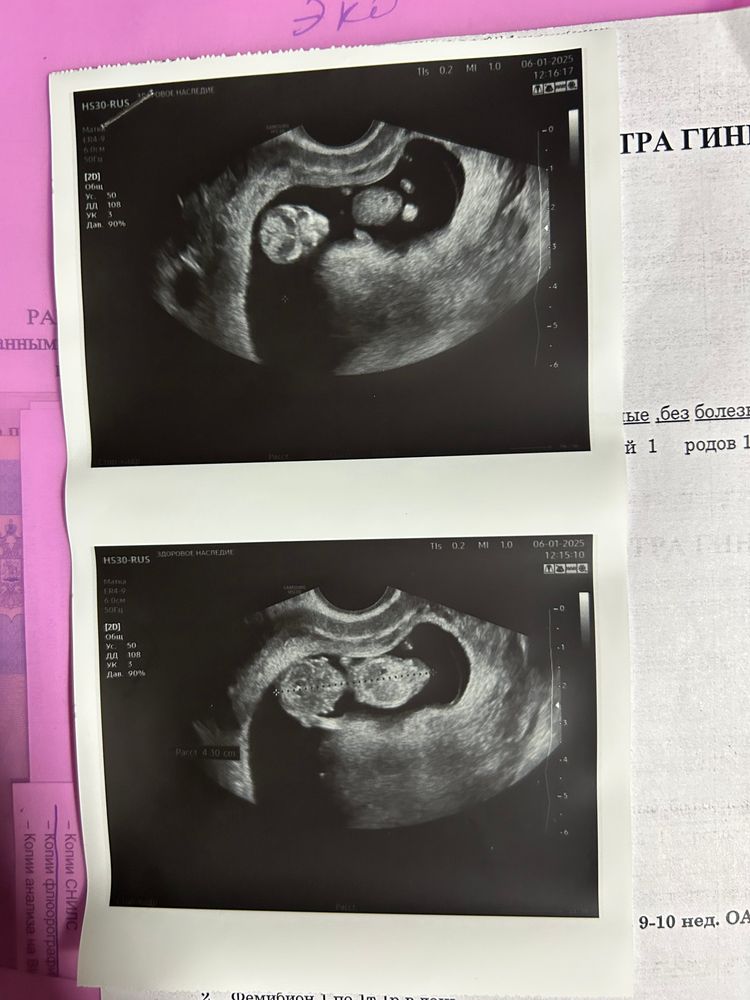

Ну вам же должны были написать на сколько ваше ктр соответствует) У меня в 11.5 было 44,2мм- это соответствует 11.2))

Ксения, у вас соответствует 11н, не переживайте

Ксения, это размер до копчика, есть в таблицах размеры с ножками, это важно, разница огромна!

Сова, я посмотрела, мы по ни дней границе нормы

У нас в 12+1 размер был 50мм ровно)